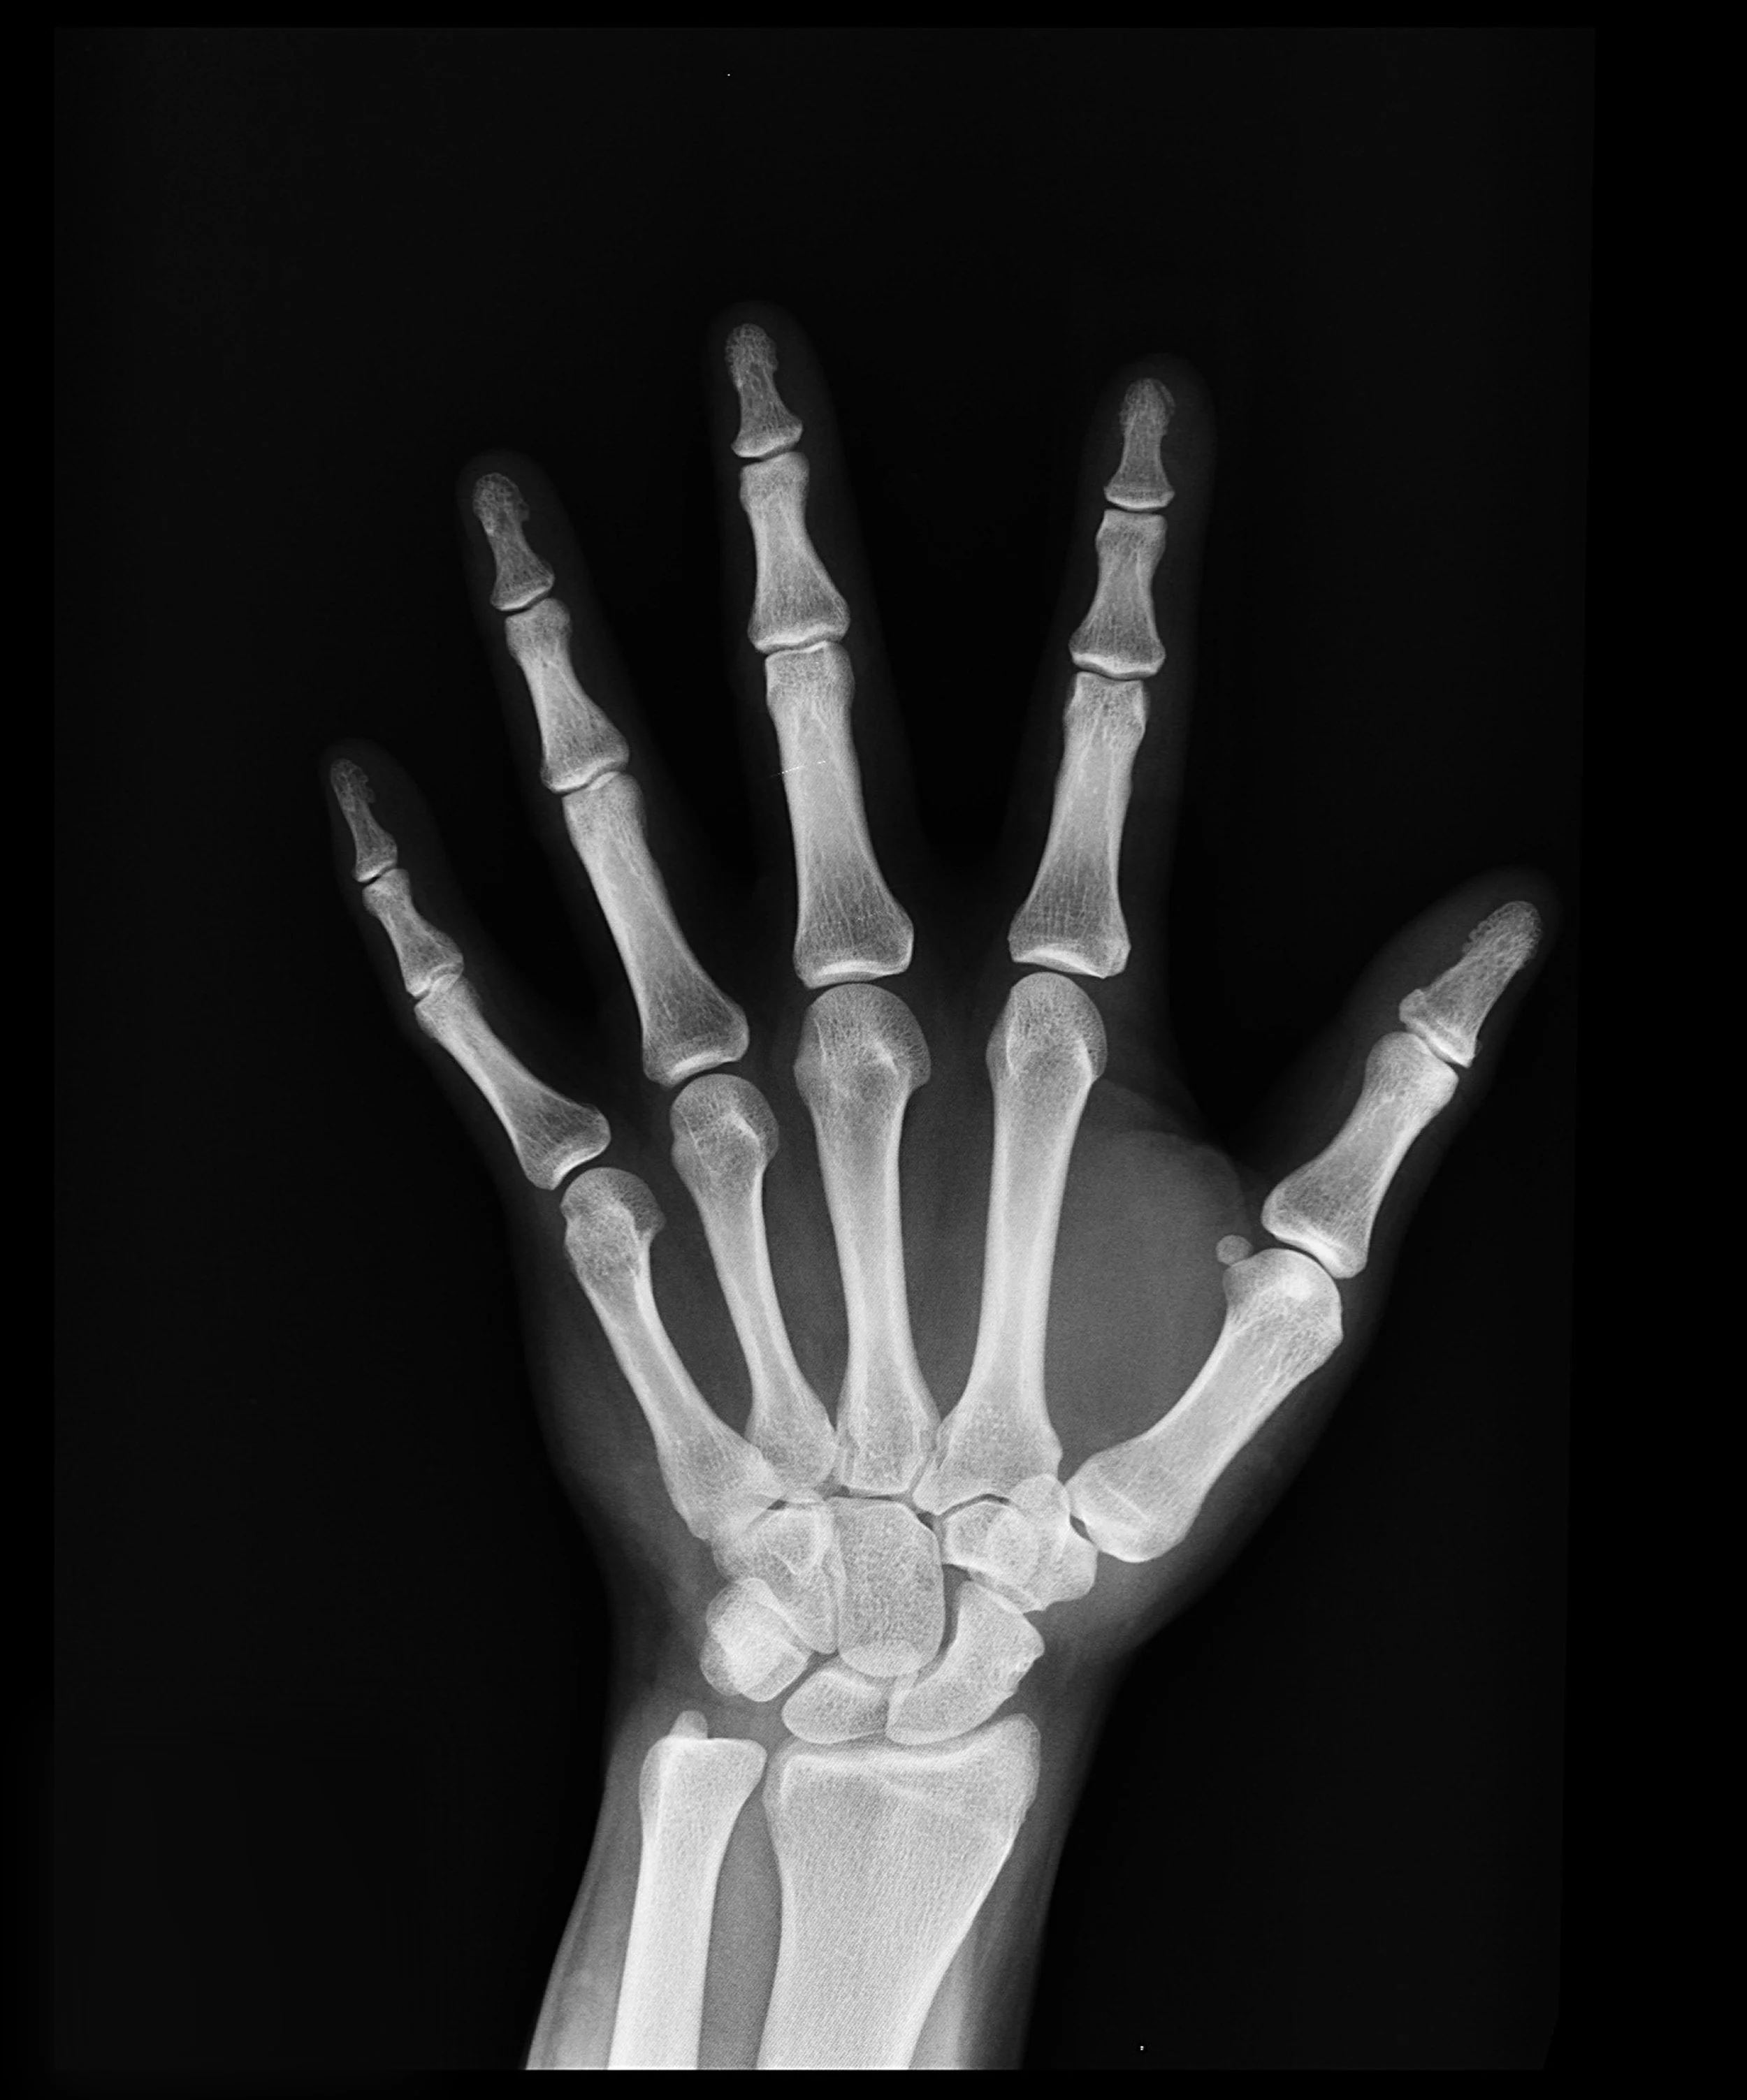

Fracture management

Fractures & Their Management